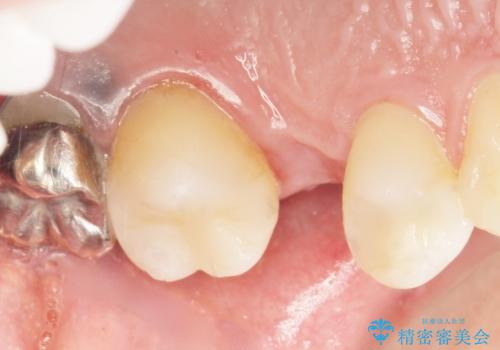

う蝕を丁寧に除去したのち、セラミックインレーによる修復を行いました。

審美的な仕上がりと自然な咬み心地に喜んで頂けました。

インプラント治療と並行して虫歯治療を行うことで、治療期間の短縮を図ることができました。

インレーの種類:セラミックインレー(e-max press)